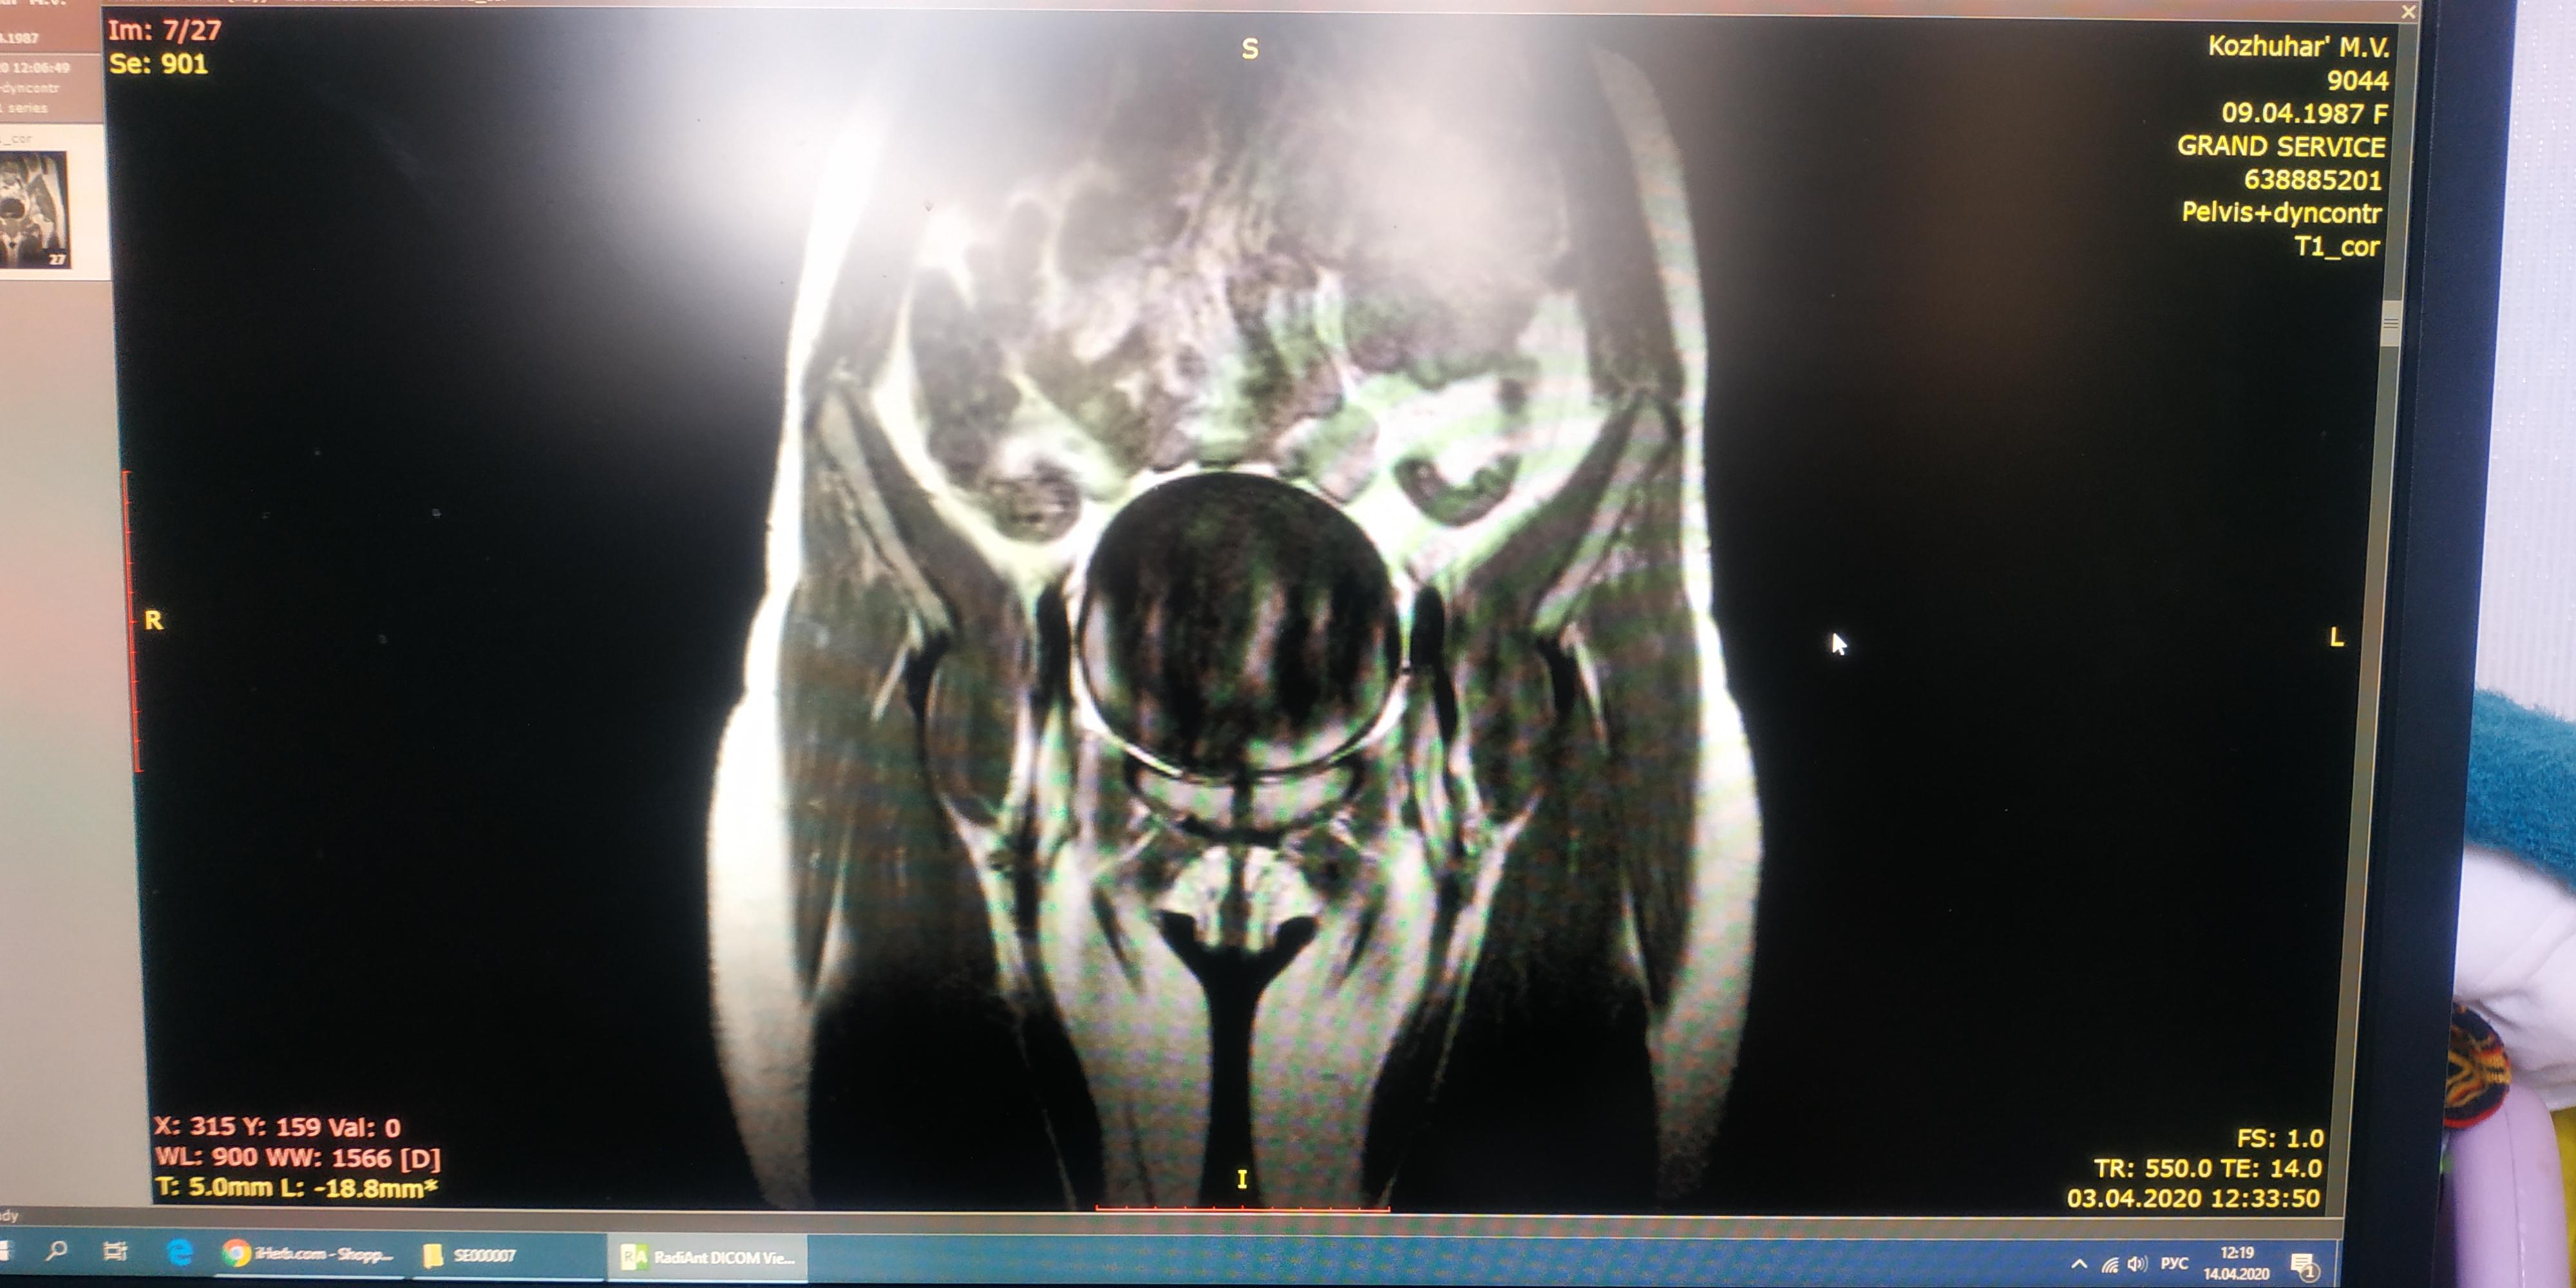

На протяжении нескольких лет мучает цистит(ну я думаю что это цистит). Боли бывает начинаются перед месячными, овуляцией или просто когда слегка замерзну. Чувство как-будто хочешь писать, но не можешь...будто что-то восполилось оттекло и не даёт моче выйти. Иногда в моче присутствует кровь. Пью Фурадонин вроде становится полегче, но не не совсем.

Анализы мочи всегда разные. Может надо какое-то обследование пройти, может это не просто цистит? Подскажите пожалуйста, что делать.

Здравствуйте! Надо сделать анализ мочи на бакпосев до лечения или после, но не ранее, чем через месяц после последнего приёма последнего антибактериального препарата по любому поводу. Сделайте УЗИ почек и УЗИ мочевого пузыря с регистрацией мочеточниковых выбросов и определением объёма остаточной мочи. Также обязательно посетить гинеколога( который,вероятно, назначит своё обследование). По результатам обследования можно будет планировать лечение.